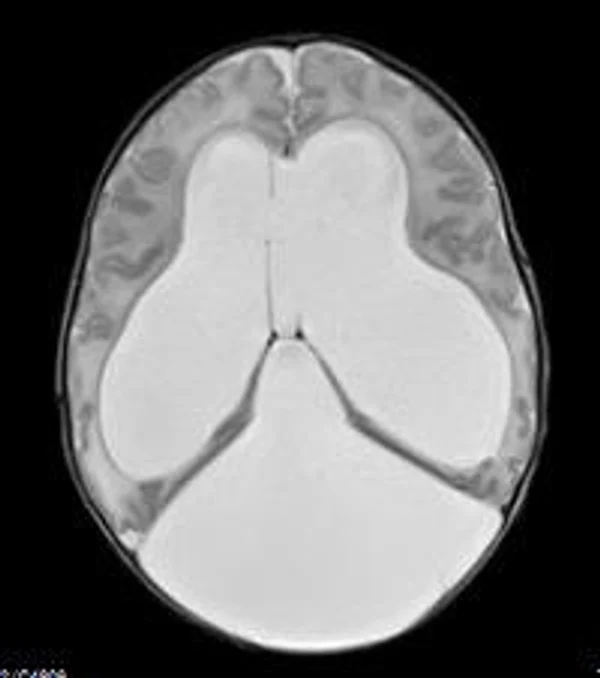

кисты, аномалии Денди-Уокера и др.Операции при внутричерепных кистах. В основном встречаются арахноидальные кисты различных локализаций и кисты сосудистых сплетений боковых желудочков. Пациентам с врождёнными кистами операции проводятся в следующих ситуациях: увеличении объема кисты в динамике, наличии клинических проявлений, компрессии и дислокации мозговых структур, наличии окклюзии ликворных путей. Нами используются 2 способа хирургического лечения кист: эндоскопическая перфорация стенок кист и открытая резекция кист. Открытая резекция кист проводится при ретроцеребеллярных арахноидальных кистах (рис. 2), при арахноидальных кистах межполушарной щели при отсутствии непосредственного контакта их стенок со стенками расширенных желудочков головного мозга и повторного увеличения кист средней черепной ямки после эндоскопической кисто-цистерностомии. Техника операции заключается в проведение краниотомии и максимальном иссечении стенок кист с созданием широкого сообщения кист с субарахноидальным пространством. Эндоскопические операции проводятся при арахноидальных кистах межножковой и пинеальной цистерн, арахноидальных кистах межполушарной щели при тесном контакте их стенок со стенками расширенной желудочковой системы (рис. 3), первично при арахноидальных кистах средней черепной ямки, а также при кистах сосудистых сплетений боковых желудочков. При арахноидальных кистах межножковой цистерны эндоскопически проводится перфорация стенок кисты, сообщая ее с просветом III желудочка и межножковой цистерной – эндоскопическая вентрикуло-кисто-цистерностомия (рис. 4). При арахноидальных кистах пинеальной цистерны проводится перфорация кисты в передне-верхних её отделах с созданием сообщения полости кисты с просветом III желудочка – эндоскопическая кисто-вентрикулостомия. С целью предотвращения облитерации сформированного отверстия иногда в полость кисты под контролем эндоскопа вводится стент перфорированный на протяжении (рис. 5, 6). Эндоскопическая кисто-цистерностомия выполняется при арахноидальных кистах средней черепной ямки. При этом создается широкое сообщение кисты с базальными цистернами. При кистах сосудистых сплетений боковых желудочков проводится их вскрытие в просвет боковых желудочков – эндоскопическая кисто-вентрикулостомия. При множественных кистах проводится их хирургическое сообщение между собой – интеркистосмия